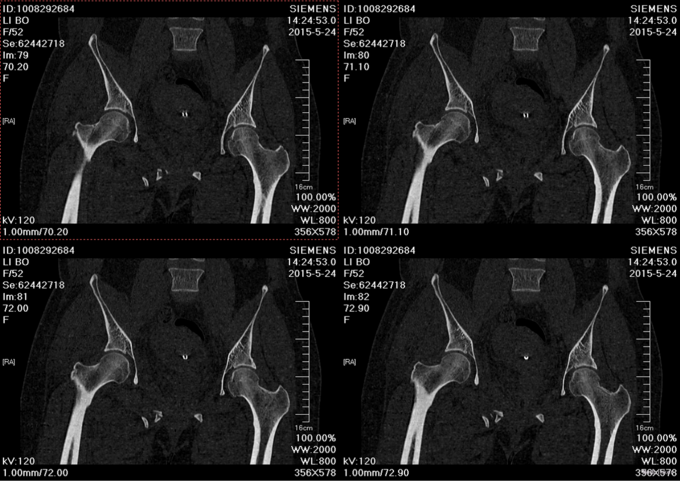

主诉:外伤后右髋部疼痛肿胀8天 现病史:患者于2015年5月16日发生车祸,伤后右髋部疼痛肿胀,下肢运动障碍,急诊120送至丹东市二医院,行骨盆平片,骨盆CT提示骨盆骨折,给予输血补液、骨牵引及留置尿管等对症治疗,急诊以“骨盆骨折”为主要诊断收入我科,患者病来无头晕头痛,无恶心呕吐,留置导尿中,大便正常。

诊断:骨盆骨折(Tile B1) 患者入院后完善检查后,全麻下行骨盆骨折切开复位钢板内固定术,术后给予抗炎,消肿,冷敷,患肢抬高等对症治疗。患者每天换药观察切口愈合情况,无红肿及渗出,待伤口14天后予以拆线治疗,予以出院,给予康复处方。